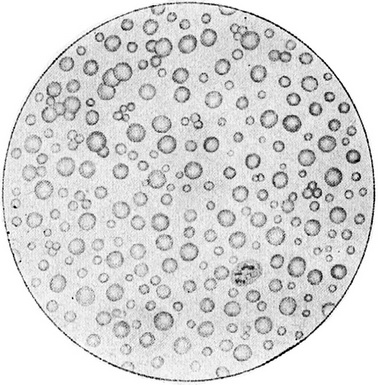

Під мікроскопом зріле молоко подається у вигляді рівномірної суспензії жирових кульок більш або менш однакової величини (рис. 91); в 1 мм їх міститься близько 5000000. Молозивных тілець в хорошому зрілому молоці немає, але вони можуть з'являтися при ранньому згасання лактації, наприклад в результаті систематичного неповного звільнення грудних залоз від молока при годуванні, а також при інших моментах, так чи інакше пригнічують секрецію.

Рис. 91. Зріле жіноче молоко під мікроскопом.